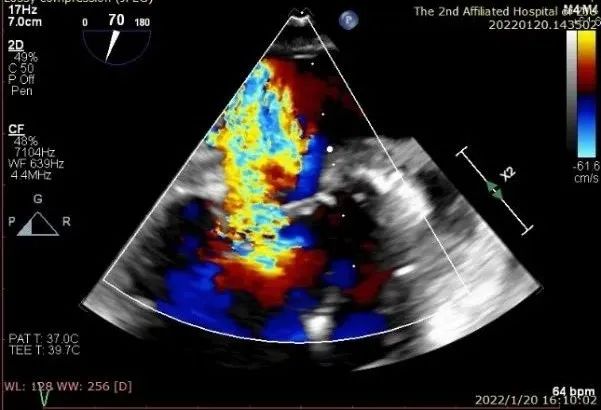

患者一术前二尖瓣反流重度4+

患者二术前二尖瓣反流4+